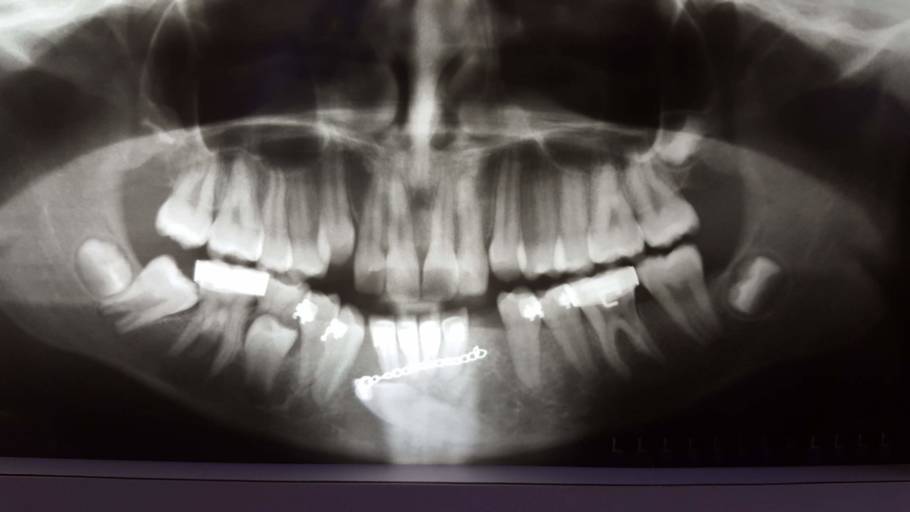

What can this be?

I went for a wisdom tooth removal but they found this space under tooth #24 after doing my X-ray examination.. I’m really scared that I might loose the tooth or have to have a tooth removed. I don’t have any pain with the tooth and no problems as to...